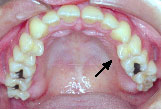

下の歯が上の歯より前に出て前歯は咬めていません。左上の第2小臼歯は骨の中に埋まっています。

クォードヘリックスで上顎歯列を左右へ拡げた後、右上第1小臼歯を抜歯し、エッジワイズブラケットを付けて術前矯正を始めました。

骨の中に埋まっている左上の第2小臼歯は手術の時に抜いてもらいます。